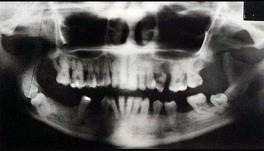

问题 关于快速进展性牙周炎,哪项正确 ( )

选项 A.所有患者都有中性粒细胞及单核细胞的功能缺陷 B.有严重及快速的骨破坏,然后破坏过程自然停止或显著减慢 C.发病年龄青春期至25岁之间 D.病损好发于第一恒磨牙和上下前牙 E.本病极少伴有全身症状

答案 B